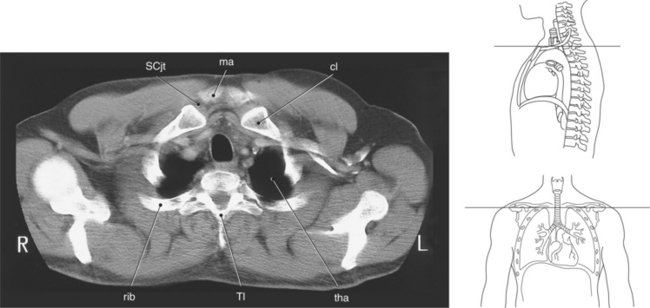

Figure 6.5 Axial CT scan of thoracic inlet.

Key: ma, Manubrium; sta, sternal angle; b, body; tho, thoracic outlet; SCjt, sternoclavicular joint; cl, clavicle; tha, thoracic aperture; T1, first thoracic vertebra; rib, first rib.

The bony thorax functions to protect the organs of the thorax and to aid in respiration. It consists of the thoracic vertebrae, sternum, ribs, and costal cartilages (Figure 6.2). The 12 thoracic vertebrae make up the posterior boundary of the thoracic cage. The anterior boundary is created by the sternum, located midline. The sternum has three components: manubrium, body, and xiphoid process (Figures 6.3 and 6.4). The triangular-shaped manubrium is the most superior portion and articulates with the first two pairs of ribs and the clavicles. It articulates with the clavicle at the clavicular notch to form the sternoclavicular joints (Figure 6.5). A common landmark, the jugular notch, is located on the superior border of the manubrium at approximately the level of T2-T3. The manubrium and body of the sternum come together at an angle to form a ridge known as the sternal angle, which is located at approximately the level of T4-T5. The slender body of the sternum has several indentations along its sides where it articulates with the cartilage of the third through seventh ribs (Figures 6.6 and 6.7). The small xiphoid process is located on the inferior border of the sternum and is a site for muscle attachments (Figure 6.8).

There are two openings, or apertures, associated with the bony thorax. The superior aperture is formed by the first thoracic vertebra, first pair of ribs and their costal cartilages, and manubrium. This aperture, known as the thoracic inlet, allows for the passage of nerves, vessels, and viscera from the neck into the thoracic cavity. The inferior aperture is much larger and is made up of the twelfth thoracic vertebra, twelfth pair of ribs and costal margins, and xiphoid sternal junction. This aperture is known as the thoracic outlet (Figures 6.2, 6.5, and 6.8).